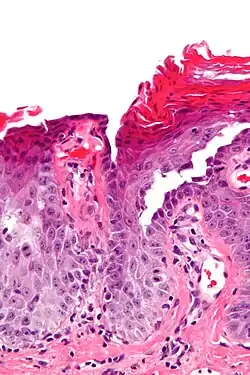

Micrograph of transient acantholytic dermatosis, showing subcorneal separation and acantholysis. H&E stain.

Grover's disease (GD) is a polymorphic, pruritic, papulovesicular dermatosis characterized histologically by acantholysis[2]: 529  with or without dyskeratosis.[3] Once confirmed, most cases of Grover's disease last six to twelve months, which is why it was originally called "transient". However it may last much longer. Nevertheless, it is not to be confused with relapsing linear acantholytic dermatosis.

Grover's may be suspected by its appearance, but since it has such a characteristic appearance under the microscope a shave skin or punch biopsy is often performed.